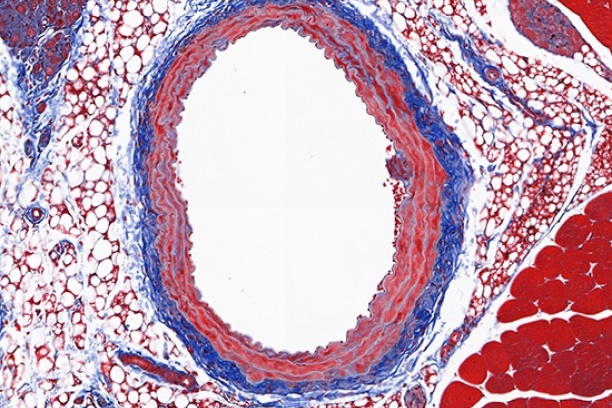

The Digital Histology Shared Resource provides large-scale digital archiving and quantitative analysis of histologic, immunohistochemical and immunofluorescence staining of tissue sections and tissue microarrays. Two Aperio Versa automated scanning microscopes, and Aperio AT2 and a Leica SCN400 Slide Scanner deliver solutions for high-resolution imaging in both bright field and fluorescence. All instruments have high-capacity robotic autoloading (200 slides for the Aperio Versa and Aperio AT2 and 384 slides for the Leica SCN400) making them ideal for large slide cohorts and tissue microarrays. The associated software packages provide complex algorithms for unbiased, automated image analysis and quantitation of immunostaining in both bright field and fluorescence. In addition, these systems can be utilized as a permanent high-resolution solution for those who need archiving of histologic material. The DHSR hosts a convenient, web-based digital slide-viewing environment (Digital Slide Archive) for the rapid retrieval, review, annotation and image acquisition of scanned material. This easy to use digital slide box allows researchers to share images among colleagues from any web browser while remaining in a digitally secure environment. Expert assistance is offered in planning experiments and processing data in a consistent, objective, and timely manner. The automated imaging and analysis performed in this core saves researchers and staff weeks of tedious work. An additional service offered by the DHSR is the creation of digital archives of critical and irreplaceable tissue samples, a benefit only feasible due to the automated high-resolution imaging of whole 25 mm x 75 mm microscope slides and 50 mm x 75 mm "double" slides.